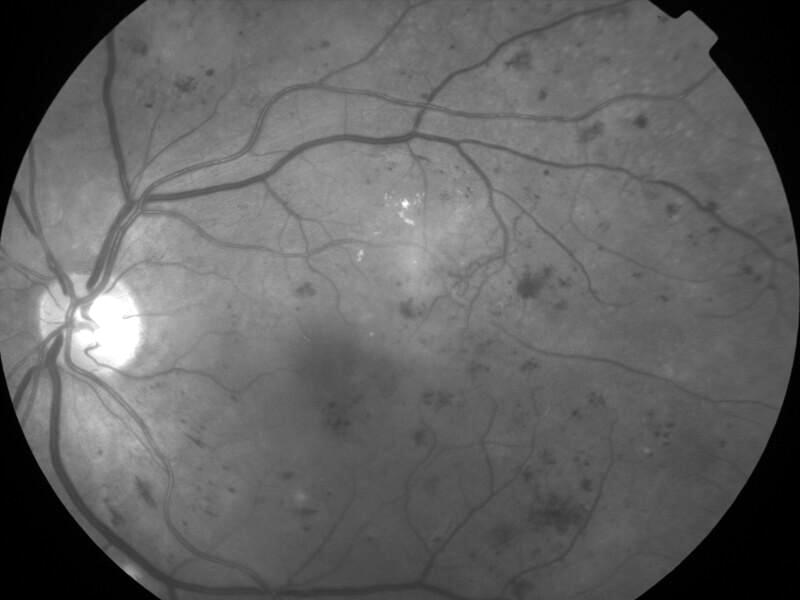

rétinopathie diabétique pré-proliférante